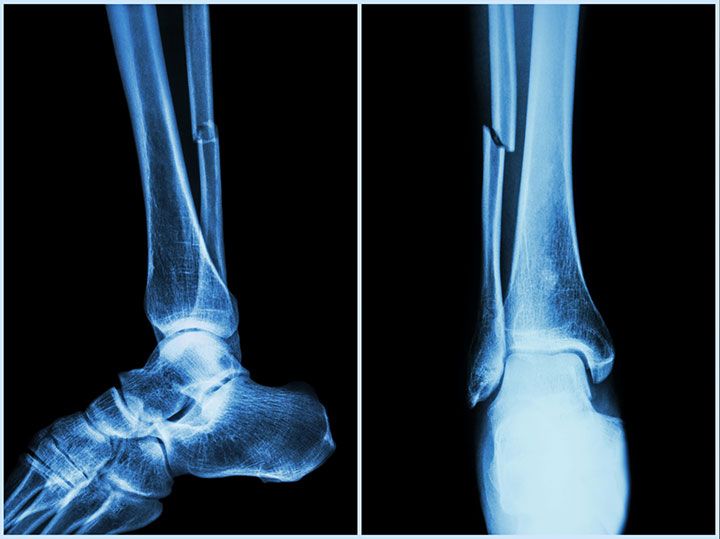

Fracturas

Una fractura del hueso es una condición de urgencia médica, es la pérdida de continuidad de un hueso y debe ser tratada de inmediato.

Después de una caída o algún traumatismo puedes identificar signos de fractura si observas hinchazón, coloración morada, dolor particularmente intenso y deformidad de la zona contundida. Si esto sucede, no dudes en contactarnos para dar un tratamiento adecuado.

El tratamiento dependerá de muchos factores; por ejemplo, del hueso fracturado, del tipo de fractura, la edad y la actividad del paciente.